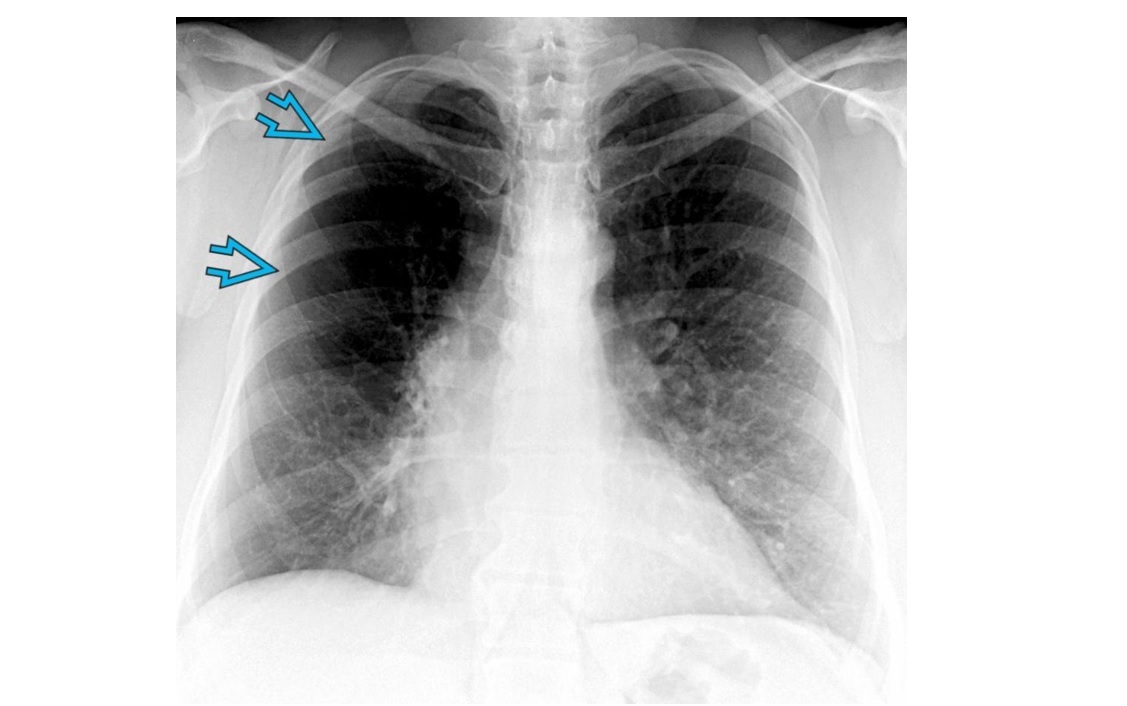

Unilateral Hypertransradiancy

-Rotation (lucent side closer to the tube ie away from the plate)

• Airway obstruction/FB

-PTx

Chest wall =

- Mastectomy

- Poland syndrome

- Polio

Swyer-james

- unilateral hyperlucent lung on radiography and air-trapping +/- bronchiectasis on CT. underdeveloped pulonary vasculatiry

- Unilateral or focal postinfectious Constrictive bronchiolitis

-emphysema